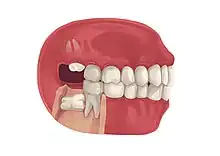

Impacted wisdom teeth is a condition where the third molars (wisdom teeth) are prevented from erupting into the mouth.[1] This can be caused by a physical barrier, such as other teeth, or when the tooth is angled away from a vertical position.[2] Completely unerupted wisdom teeth usually result in no symptoms, although they can sometimes develop cysts or neoplasms. Partially erupted wisdom teeth or wisdom teeth that are not erupted but are exposed to oral bacteria through deep periodontal pocket, can develop cavities or pericoronitis. Removal of impacted wisdom teeth is advised for the future prevention of or in the current presence of certain pathologies, such as caries (dental decay), periodontal disease or cysts. Prophylactic (preventative) extraction of wisdom teeth is preferred to be done at a younger age (middle to late teenage years) to take advantage of incomplete root development, which is associated with an easier surgical procedure and less probability of complications.[3]

Wisdom teeth become impacted when there is not enough room in the jaws to allow for all of the teeth to erupt into the mouth. Because the wisdom teeth are the last to erupt, due to insufficient room in the jaws to accommodate more teeth, the wisdom teeth become stuck in the jaws, i.e., impacted. There is a genetic predisposition to tooth impaction. Genetics plays an important, albeit unpredictable role in dictating jaw and tooth size and tooth eruption potential of the teeth. Some also believe that there is an evolutionary decrease in jaw size due to softer modern diets that are more refined and less coarse than our ancestors'.[6]